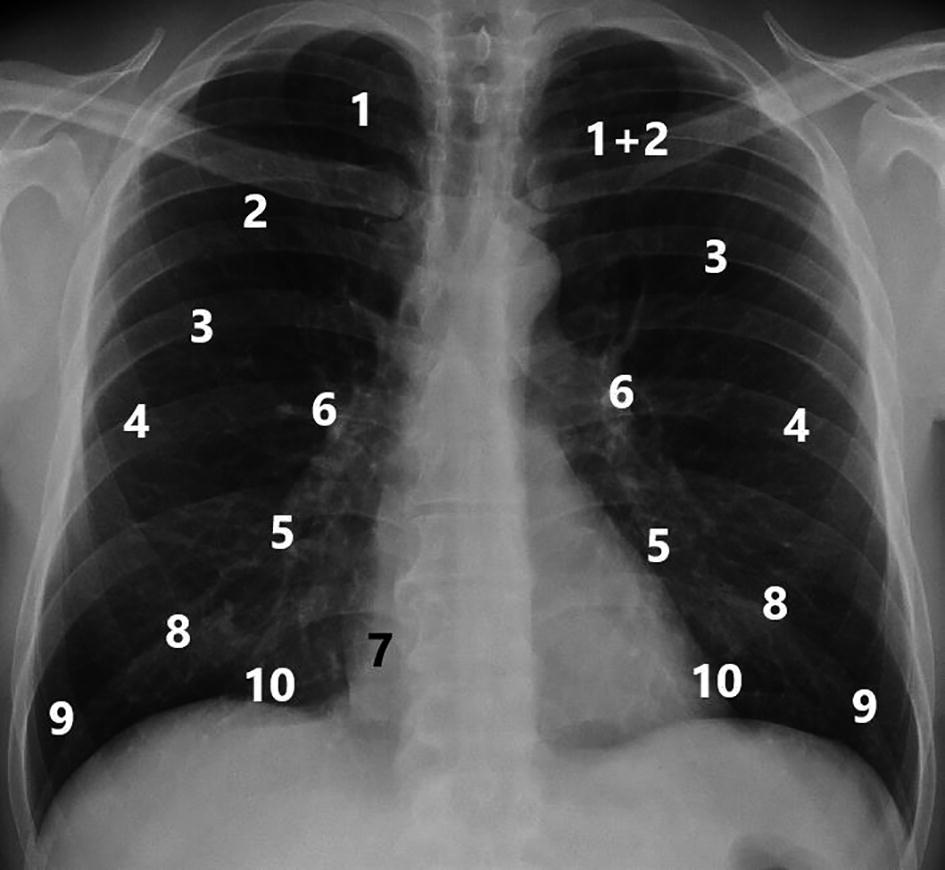

Beschreibung In diesem Tutorium erarbeiten wir mit Euch die strukturierte Befundung eines konventionellen RöntgenThorax Es werden dabei zunächst kurz die anatomischen Strukturen besprochen und einige wichtige Pathologien als Beispiele aufgezeigt. Vor der Befundung werden die Patientendaten kontrolliert und die Bildqualität beurteilt Bei der Befundung eines RöntgenThorax sollte man immer nach dem gleichen Schema vorgehen, um nichts zu übersehen Ein Beispiel ist das Vorgehen von außen nach innen, also angefangen mit der Thoraxwand und endend beim Mediastinum Bei Betrachten der Thoraxwand werden der Weichteilmantel und die. Röntgen thorax befundung lernen Klimmzüge lernen Guide und FortschrittsplanMYPROTEIN Hohe Qualität, große Auswahl und faire Preise Besuche unseren Shop noch heute Nr 1 Mehr als 3,6 Millionen monatliche Besucher und 8100 Verkäufer vertrauen uns bereits.

Kopf Gadovist Berufspolitik MTRA Thorax Onkologie Ultravist Technik Injektoren StrahlenDosismanagement Prostata Qualitätssicherung Leber Galle Künstliche Intelligenz Bewegungsapparat Computertomographie Strukturierte Befundung Strahlenexposition Pädiatrie Früherkennung Screening EURATOM Kontrastmittel Innovation ZNS Röntgen Ultraschall. Dieser Kurs gibt dir einen fundierten Überblick über die Grundlagen (technisch, anatomisch, radiologisch), Indikationen, Qualitätskriterien der Aufnahme und strukturierte Befundung eines RöntgenThorax. Durch das Erlernen der technischen Grundlagen, der systematischen Befundung und der im Thoraxröntgenbild erkennbaren Anatomie erhalten Sie das Rüstzeug zur Beurteilung von Thoraxröntgenbildern In den Modulen, die nach Anatomie und Pathophysiologie gegliedert sind, befinden sich jeweils die gleichen Bilder.

Systematische Befundung von RöntgenThoraxAufnahmen Intensiv – Workshop für Einsteiger Zielgruppe Röntgenaufnahmen des Thorax zählen zu den häufigsten Untersuchungen, die auch für nichtRadiologen in Nachtdiensten oder in der täglichen Routine anfallen Dieser Kompaktkurs richtet sich an alle Ärztinnen und Ärzte, die sich systematisch in eine sichere Befundung konventioneller. Welche knöchernen Strukturen und welche Weichteile stellen sich dar?. 1 Definition Als RöntgenThorax wird die standardisierte Untersuchung des Thorax durch Anfertigen von Röntgenaufnahmen in posterioranteriorem und seitlichem Strahlengang bezeichnet Ein RöntgenThorax gehört für viele medizinische Prozeduren (zB vor operativen Eingriffen) zur Basisdiagnostik 2 Technik Die Aufnahmen werden heute in der Regel in Hartstrahltechnik als paProjektion.